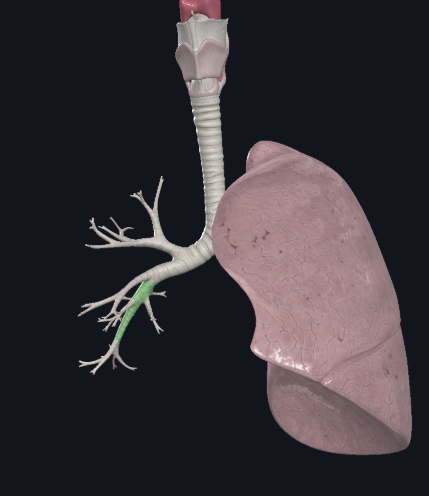

What structure is this?

Right main bronchus

What structure is this?

Right superior lobar bronchus

What structure is this?

Middle Lobar bronchus

What structure is this?

Right inferior lobar bronchus

What structure is this?

Left main bronchus